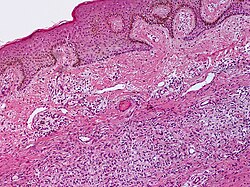

Histoplasmosis in skin

A. Extending from papillary dermis into dermis is a chronic, blue inflammatory infiltrate. B. The infiltrate comprises lymphocytes, plasma cells, and macrophages. C. At the edge of the biopsy pink strews inflammatory cells; this pink invasion of inflammation, so to speak, is a good place to look for organisms. D. High power reveals sometimes budding yeast forms in clear spaces.